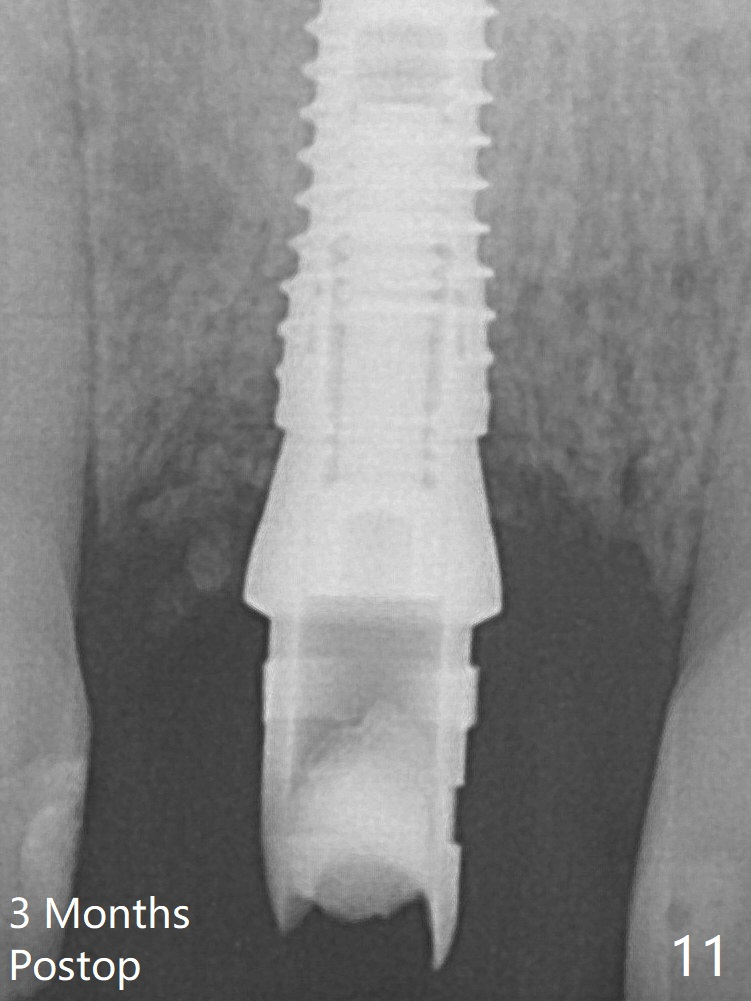

The initial osteotomy depth is 16 mm (Fig.5); the trajectory is going to be adjusted as shown by arrows. The trajectory improves when a 3.8x15 mm dummy implant is placed (Fig.6). The definitive implant (3.8x16 mm) appears to be placed at an appropriate level (Fig.7). A 4.5x3 mm temporary abutment is inserted for an immediate provisional. As routine, Vera Graft is placed in the buccal gap. Although the provisional. is unstable, there is no bone loss 2 months 20 days postop (Fig.9). Because of the loose provisional (detachment from the underlying temporary abutment), impression is taken earlier (3 months postop, Fig.10,11). Due to the pointed abutment tip, the crown is redone 3 times. By the time of cementation (nearly 5 months postop), the socket appears to have healed (Fig.12 (4.5x5(4) mm cemented abutment)).